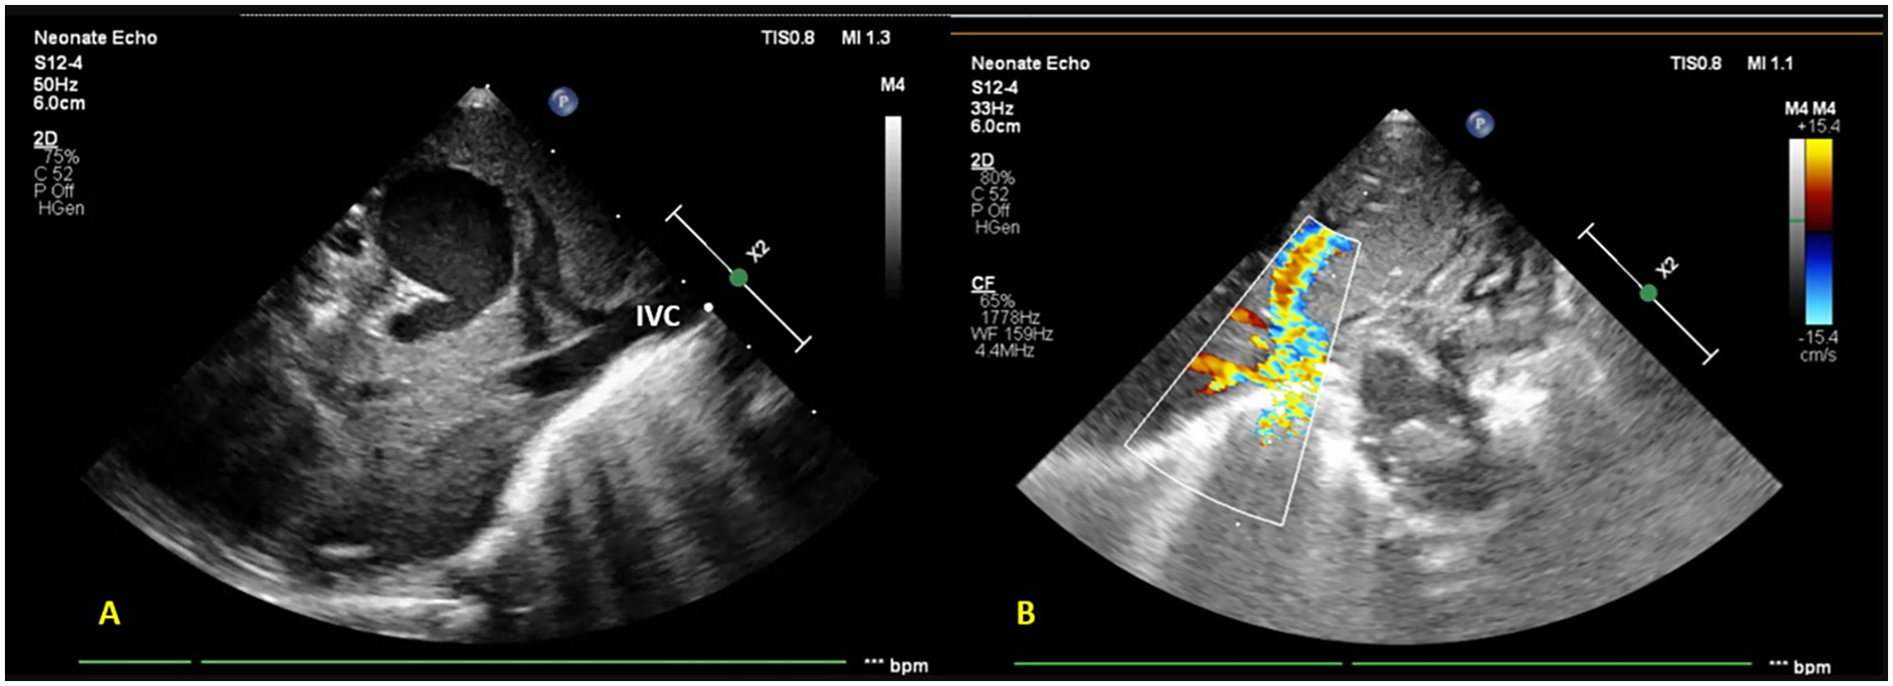

On admission, the infant was normothermic, with tachycardia, tachypnea, and subcostal and intercostal retractions; oxygen saturation (SpO2) was 88% on room air. Continuous positive airway pressure (CPAP) support with binasal prongs was commenced, with an oxygen requirement of 30% to maintain SpO2 of >90%. No pre-post ductal saturation difference was noted. A provisional diagnosis of meconium aspiration syndrome (MAS) with suspected sepsis was made. Blood investigations revealed a normal hemogram and CRP. A chest radiograph was suggestive of bilateral non-specific air space opacities. A routine screening FnECHO revealed features of mild-to-moderate pulmonary hypertension with PASP ≈45 mmHg, small left atrium (LA), right to left flow across the PFO, normal cardiac outputs, and cardiac systolic function. A subcostal echocardiographic imaging unexpectedly revealed a saccular hypo-echogenicity in the liver. Doppler ultrasound confirmed its vascular nature. On further interrogation, all pulmonary veins were noted to be draining into a chamber confluence and then descending into a large vessel joining the IVC (Figure 2).

Figure 2

Subcostal imaging and targeted liver POCUS views reveal (A) a saccular hypo-echogenicity in the liver (likely a venous confluence draining into the portal tract) further draining into the inferior vena cava (B) color Doppler showing an anomalous vessel with turbulent flow.

The findings suggested an infra-diaphragmatic obstructed TAPVC with moderate pulmonary hypertension, which was confirmed by the pediatric cardiologist. The infant was referred to a cardiac surgery center for early definitive surgical repair.